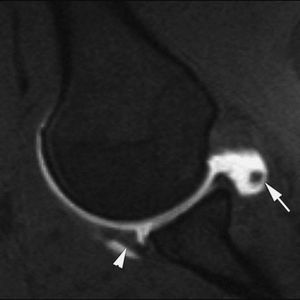

El síndrome de choque anterior es una causa relativamente frecuente de dolor crónico de tobillo, especialmente en deportistas sometidos a estrés repetido del tobillo en dorsiflexión («tobillo de futbolista»). Este proceso produce la existencia de prominencias óseas en el margen anterior del techo tibial, generalmente asociadas a otras en el área correspondiente sobre el margen opuesto del astrágalo. Estos osteofitos pueden chocar entre sí, especialmente con la dorsiflexión del tobillo, y atrapar tejidos de partes blandas. La RMA es de gran utilidad en la valoración de la afectación condral y la sinovitis (fig. 11) en el receso capsular anterior del tobillo19,23.

Fig. 11.--Síndrome de choque anterior. Corte sagital de RMA potenciado en T1 en el que se observan espolones óseos en el reborde tibial anterior y en la vertiente dorsal del cuello del astrágalo (flechas).